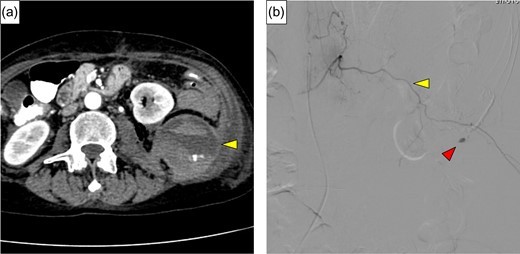

A 54-year-old woman was referred to our hospital because of abdominal pain. She had a history of adult Still’s disease at age 49 and underwent treatment with oral prednisolone, 90 mg/day and cyclosporine, 175 mg/day. A physical examination revealed deep tenderness in the abdomen. Laboratory data showed slight leukocytosis (white blood cell count 9100/μL) with a moderately elevated C-reactive protein level (9.3 mg/dL), while other data, including blood coagulation factor, were within normal ranges. Computed tomography (CT) revealed a small amount of extra-intestinal free air around the rectum and massive retroperitoneal emphysema between the rectum and the left kidney (Fig. 1a and b). Arterial aneurysm was not confirmed. Based on a preoperative diagnosis of rectal perforation, emergency laparotomy was performed, which confirmed peritoneal fluid collection (Fig. 2) and rectum perforation on the retroperitoneal side. After aspiration of the pus and irrigation of the area with saline, Hartmann’s operation was performed (Fig. 3a). Although she was undergoing immunosuppressive treatment, pathological study disclosed no association between diverticulum perforation and cytomegalovirus enteritis (Fig. 3b). On postoperative Day 4, she suffered a sudden intolerable left flank pain; her hemoglobin level was 7.5 g/dL, and slight prolongation of prothrombin time was recognized. CT revealed a left retroperitoneal hematoma and extravasation from the left first lumbar arteries (Fig. 4a). Emergency transarterial angiography and lumbar artery embolization was performed (Fig. 4b). On Day 20 after the first operation the patient felt a sudden right flank pain, and CT confirmed intra-abdominal free air (Fig. 5a). A second emergency laparotomy was performed, which revealed cecal perforation with no obvious masses (Fig. 5b). Perforation resulting from diverticulum was suspected, and an ileostomy without intraperitoneal anastomosis was performed because of concern about anastomotic leakage. Postoperatively the patient developed an intra-abdominal abscess, surgical site infection (Clavien-Dindo IIIa) and pneumonia (Clavien-Dindo II), which were treated conservatively. Although it took time to rehabilitate the patient and control the adult Still’s disease, she was discharged on Day 212 after the first operation. The patient is now doing well with comfortable activity of daily life.

(a) Contrast extravasation from lumbar artery and hematoma expansion lifting the left kidney was identified (yellow arrow). (b) Angiography revealed extravasation of contrast medium (red arrow) from the left first lumbar artery (yellow arrow).